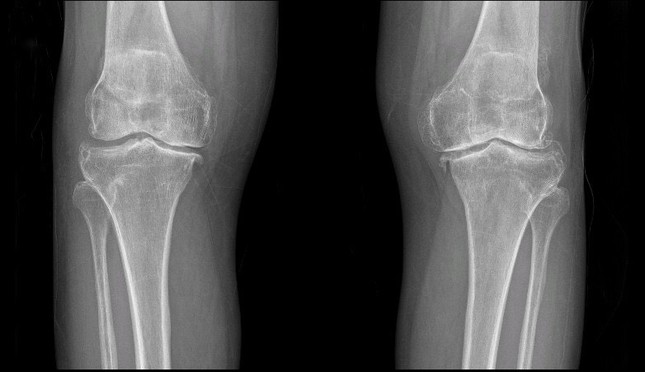

Khám lâm sàng và chẩn đoán hình ảnh: Thực hiện X-quang, MRI hoặc CT để xác định mức độ tổn thương khớp và lựa chọn loại khớp nhân tạo phù hợp.

Chụp X-Quang đánh giá tình trạng khớp trước phẫu thuật

Tái khám định kỳ: Bác sĩ kiểm tra tiến triển phục hồi, chụp X-quang đánh giá vị trí khớp nhân tạo và điều chỉnh kế hoạch tập luyện nếu cần.

Đây là nguyên nhân phổ biến nhất. Khi lớp sụn khớp bị mòn gần hết, hai đầu xương cọ xát vào nhau gây đau dữ dội, sưng, cứng khớp và biến dạng trục chân. Người bệnh khó đi lại, leo cầu thang hoặc thậm chí đau ngay cả khi nghỉ ngơi. Khi hình ảnh X-quang cho thấy khe khớp hẹp, mọc gai xương và khớp bị hư hại nặng, bác sĩ có thể chỉ định thay khớp gối để khôi phục chức năng.